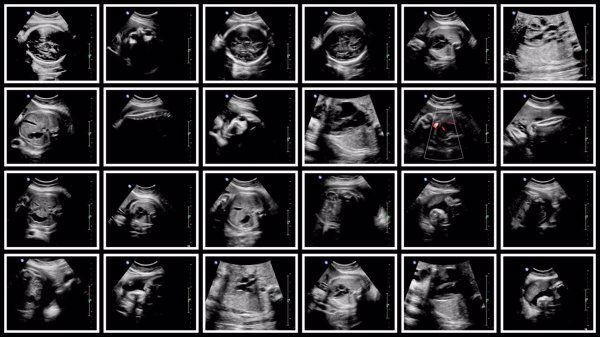

怀孕期间可以通过定期的产前检查以及超声波检查来监测胎儿的健康状况。

在整个妊娠期,需要定期进行血常规、尿常规、甲状腺功能测定、唐氏筛查、羊水穿刺术等检查项目,以确保母体及胎儿的健康。同时还需要配合医生的意见,做好日常护理工作,如均衡饮食、规律作息、适当运动等,有利于促进身体健康。

如果孕妇存在染色体异常或既往有不良孕产史,则可能需要更频繁地进行胎儿健康评估,通常建议在孕期16-20周之间开始进行无创DNA检测或羊水穿刺术。